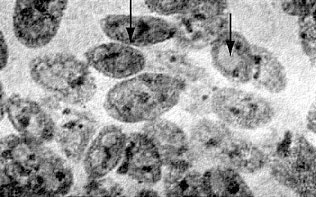

Причины этого заболевания, известного под названием подострый склерозирующий панэнцефалит (сокращенно – ПСПЭ), долгое время оставались неизвестными. Но вот с середины 1960-х годов исследованием ПСПЭ начинают заниматься вирусологи. А побудило их к этому обнаружение Дж. Даусоном в клетках головного мозга погибших от ПСПЭ детей определенных образований (рис. 10). Данная находка заинтересовала ученого потому, что подобного рода структуры, называемые тельцами включений, нередко образуются в клетках разнообразных тканей при вирусных заболеваниях: оспе, бешенстве, герпесе, кори, эпидемическом конъюнктивите, гриппе, аденовирусной инфекции и др. ![]() Рис. 10. Тельца включений (показаны стрелками) в культуре клеток мозга, полученных от пациента, страдавшего подострым склерозирующим панэнцефалитом Тельца включений при перечисленных заболеваниях представляют собой скопления размножающихся вирусных частиц. Они достигают значительных размеров – от 0,2 до 25 мк [8] – и могут быть круглой, овальной, удлиненной или эллипсовидной формы. Их расположение в клетке неодинаково при различных заболеваниях. Так, например, при бешенстве и оспе тельца включений формируются в цитоплазме клеток, при герпесе и желтой лихорадке – в ядрах. Характер расположения, внешний вид, свойства (отношение к красителям) телец включений служат характерными признаками некоторых вирусных заболеваний, а большие размеры позволяют их легко обнаружить с помощью обычного светового микроскопа. К примеру, обнаружение телец включений играет важнейшую роль в лабораторной диагностике таких вирусных заболеваний, как бешенство и оспа. А теперь, читатель, ответьте на такой вопрос – что интересует врача, выслушавшего жалобы больного, в первую очередь? Да, безусловно, его анализ крови. Кровь, питающая клетки организма кислородом и снабжающая их всем необходимым для жизни, выводящая углекислоту и шлаки, постоянно присутствует во всех «уголках» нашего организма. И, несмотря на упорное стремление поддерживать свой состав на постоянном уровне, кровь, конечно же, быстрее всех других составляющих организма реагирует на происходящие сбои в его работе. А потому вирусологи прежде всего решили заглянуть в кровь больных ПСПЭ детей. Ведь если ПСПЭ – вирусное заболевание, то наверняка организм ответит образованием антител на вирус-возбудитель. Заглянули – и поразились: в крови больных ПСПЭ детей обнаруживались высокие титры противокоревых антител (титр – это наименьшее количество исследуемого материала, в котором еще определяется противовирусная активность антител). Для того чтобы оценить всю сенсационность этой находки, следует напомнить, что и у нас с вами, читатель, в крови присутствуют противокоревые антитела (ведь мы в большинстве своем переболели в детстве корью). И в нашем организме титр таких антител соответствует разведению сыворотки крови примерно 1:40. В крови же детей, страдающих ПСПЭ, титр противокоревых антител нередко достигает 1:16 000! Этот факт не говорил, он кричал! Скрупулезное изучение клеток головного мозга погибших от ПСПЭ детей подтвердило наличие в них телец включений, как две капли воды похожих на включения, характерные для вируса кори. Исследователи пошли дальше. Из мозговой ткани больных приготовили сверхтонкие срезы, которые можно рассматривать не только в световой, но и в электронный микроскоп. Этот прибор позволил выявить внутри таких телец включений большие скопления кореподобных вирусных частиц. Наконец, последнее косвенное доказательство причастности вируса кори к этому фатальному заболеванию получили с помощью метода флуоресцирующих антител. Обычные (не сверхтонкие) срезы мозговой ткани погибших от ПСПЭ детей обрабатывают иммунными сыворотками, содержащими помеченные светящимся веществом антитела к различным вирусам. Свечение тканевых срезов будет наблюдаться только в том случае, если антитела свяжутся с вирусом, находящимся в ткани. Из схемы (рис. 11) легко понять, что антитела, не соответствующие данному вирусу, не смогут с ним связаться и потому при отмывании среза ткани будут с него смыты. Если же сыворотка с меткой содержит как раз те антитела, которые соответствуют находящемуся в клетке вирусу, то они легко свяжутся с ним и отмыванием их уже нельзя будет удалить с поверхности среза. В таком препарате мы и увидим на срезе участки свечения. ![]() Рис. 11. Схематическое изображение принципа метода флуоресцирующих антител: А – в реакции использованы антитела, соответствующие данному вирусу; обработанные препараты клеток светятся (реакция положительная); Б – в реакции использованы антитела, не соответствующие данному вирусу; при промывании такого препарата не связавшиеся с вирусом (антигеном) антитела удаляются, свечения не будет (реакция отрицательная) Срезы мозговой ткани больных ПСПЭ обрабатывали различными сыворотками со светящейся меткой. Пораженные мозговые клетки светились ярким изумрудным светом только в том случае, когда срезы обрабатывали противокоревой сывороткой (рис. 12). ![]() Рис. 12. Свечение клеток мозга больного подострым склерозирующим панэнцефалитом, обработанных противокоревой флуоресцирующей сывороткой Можно было только радоваться быстрому успеху исследователей. Казалось, до получения прямого доказательства коревой природы заболевания остается всего один шаг – нужно лишь выделить из пораженной мозговой ткани коревой вирус. Но именно здесь ученых подстерегали большие трудности. И шаг этот растянулся на годы напряженнейших поисков в различных лабораториях мира. Не буду нагружать читателя подробностями различных подходов к решению данной проблемы. Отмечу лишь, что настоящий успех в поиске выпал на долю группы исследователей из Национального института неврологических заболеваний в городе Бетесде (США). Коллектив американских вирусологов, руководимый Луизой Хорта-Барбозой, применил так называемый метод смешанных культур клеток: в матрасах вырастили однослойную культуру раковых клеток человека HeLa [9] и на этот «ковер» поместили клетки мозговой ткани больного ребенка, предварительно обработанные трипсином. Прошло несколько дней, и клетки HeLa начали сморщиваться, отъединяться друг от друга, а затем и вовсе распадаться. В чем тут было дело? Оказалось, в вирусе кори! |